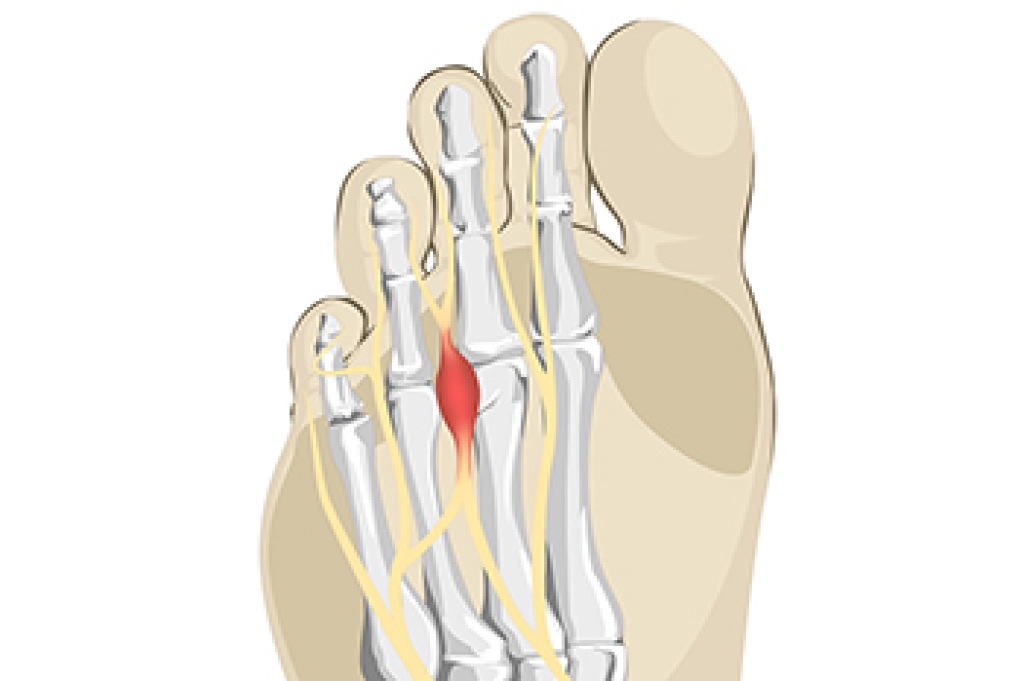

- Removing foot deformities like bunions and bone spurs

- Bunionectomy for painful bunions